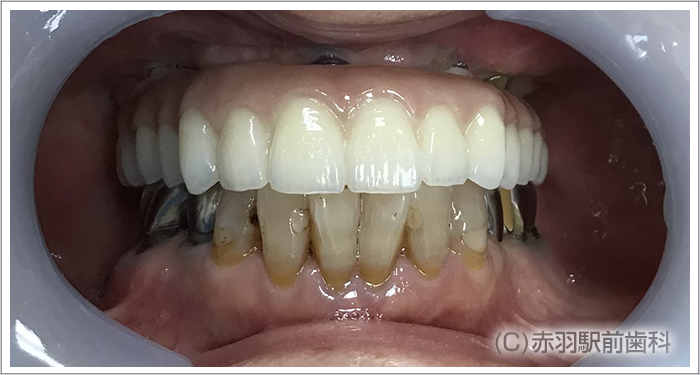

初診時の状態です。上あごのオールオン4を希望して来院しました。 ![]()

上あごの歯は全てグラグラで保存不可能な状態でした。

上顎の歯を全て抜歯してオールオン4手術をしました。

オールオン4の最終的に入る上部構造です。フルジルコニアで作製しました。

歯の裏側の形態も発音や舌感を考慮してリアルに再現しています。

フルジルコニア製の最終的な上部構造を取り付けた口腔内です。 ![]()

今後は下顎もオールオン4治療を希望しています。 |